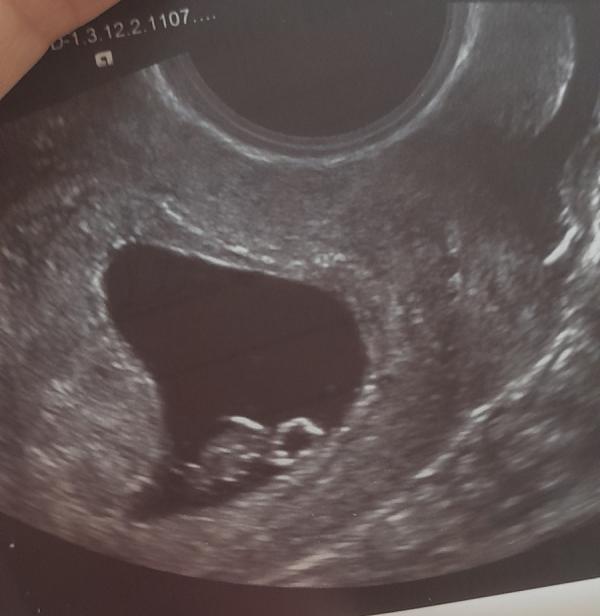

Сроку соответствуем 🥰